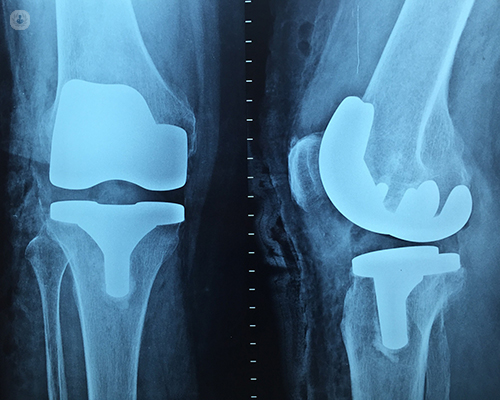

Total knee replacement is one of the most successful procedures in all of medicine. In the vast majority of cases, it enables people to live richer, more active lives free of chronic knee pain. Over time, however, a knee replacement may fail for a variety of reasons. When this occurs, your knee can become painful and swollen. It may also feel stiff or unstable, making it difficult to perform your everyday activities.

Although both procedures have the same goal — to relieve pain and improve function — revision surgery is different than primary total knee replacement. It is a longer, more complex procedure that requires extensive planning, and specialized implants and tools to achieve a good result.

Damage to the bone may make it difficult for the doctor to use standard total knee implants for revision knee replacement. In most cases, he or she will use specialized implants with longer, thicker stems that fit deeper inside the bone for extra support.

In order for a total knee replacement to function properly, an implant must remain firmly attached to the bone. During the initial surgery, the implant was either cemented into the bone or press-fit to allow bone to grow onto the surface of the implant. In either case, the implant was firmly fixed. Over time, however, an implant may loosen from the underlying bone, causing the knee to become painful.

The cause of loosening is not always clear, but high-impact activities, excessive body weight, and wear of the plastic spacer between the two metal components of the implant are all factors that may contribute. Also, patients who are younger when they undergo the initial knee replacement may "outlive" the life expectancy of their artificial knee. For these patients, there is a higher long-term risk that revision surgery will be needed due to loosening or wear.